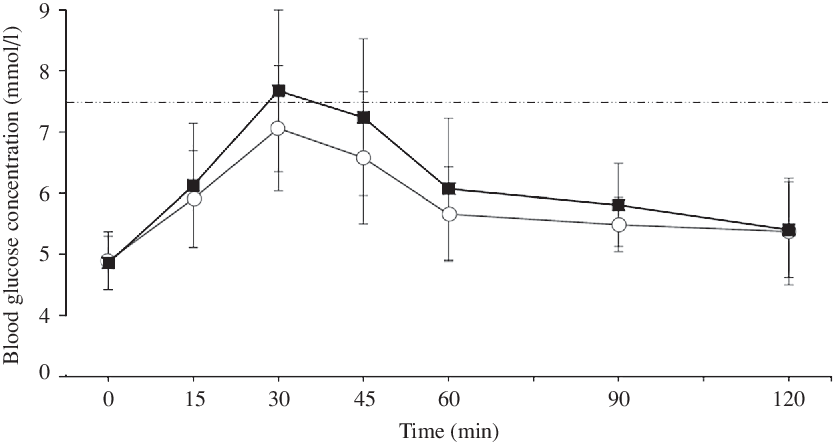

Blood glucose concentrations increased more rapidly in PRO than in CON, reaching a 7·5 % higher peak (7·9 (sd 1·4) v. 7·3 (sd 0·9) mmol/l, P = 0·049, d = 0·50, moderate effect; Fig. 3(a)) and then remaining higher than the CON trial until the final blood sample, such that there was a main effect of treatment (P = 0·037, F = 5·392) but no treatment × time interaction (P = 0·308, F = 1·241; Fig. 4). Accordingly, there was a 28·1 % mean increase in post-prandial blood glucose iAUC in the PRO condition (161·8 (sd 55·7) v. 116·3 (sd 39·2) mmol × 120 min/l (P = 0·009, d = 0·94; Fig. 3(b)). Time spent above the clinical threshold of 7·5 mmol/l blood glucose concentration was longer in the PRO trial for nine out of fourteen participants by an average of 8·2 (sd 13·4) min (15·9 (sd 17) v. 7·7 (sd 11·6) min, P = 0·039, d = 0·56, moderate effect). Although not significant (P = 0·206, d = 0·48, small effect), on average there was a 6·4 (sd 18·3) min delay in time to peak glucose with PRO (37·5 (sd 16·4) min) compared with CON (31·1 (sd 9·2) min).

Fig. 4. Blood glucose concentration following breakfast ingestion at 0 min. The dashed line represents a blood glucose concentration of 7·5 mmol/l as a reference threshold. ![]() , Control;

, Control; ![]() , protein.

, protein.